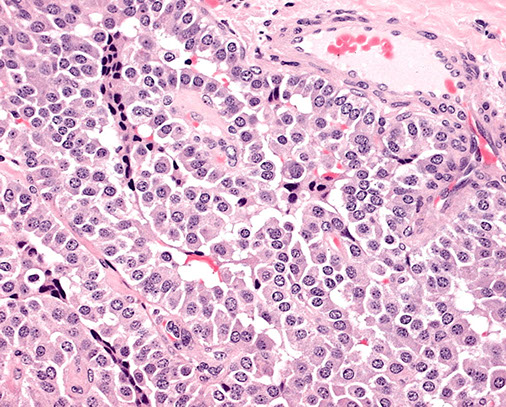

Insular carcinoma

Poorly differentiated carcinoma that grows in sheets, ribbons and cords c nuclei that look like follicular ca (not very pleomorphic)